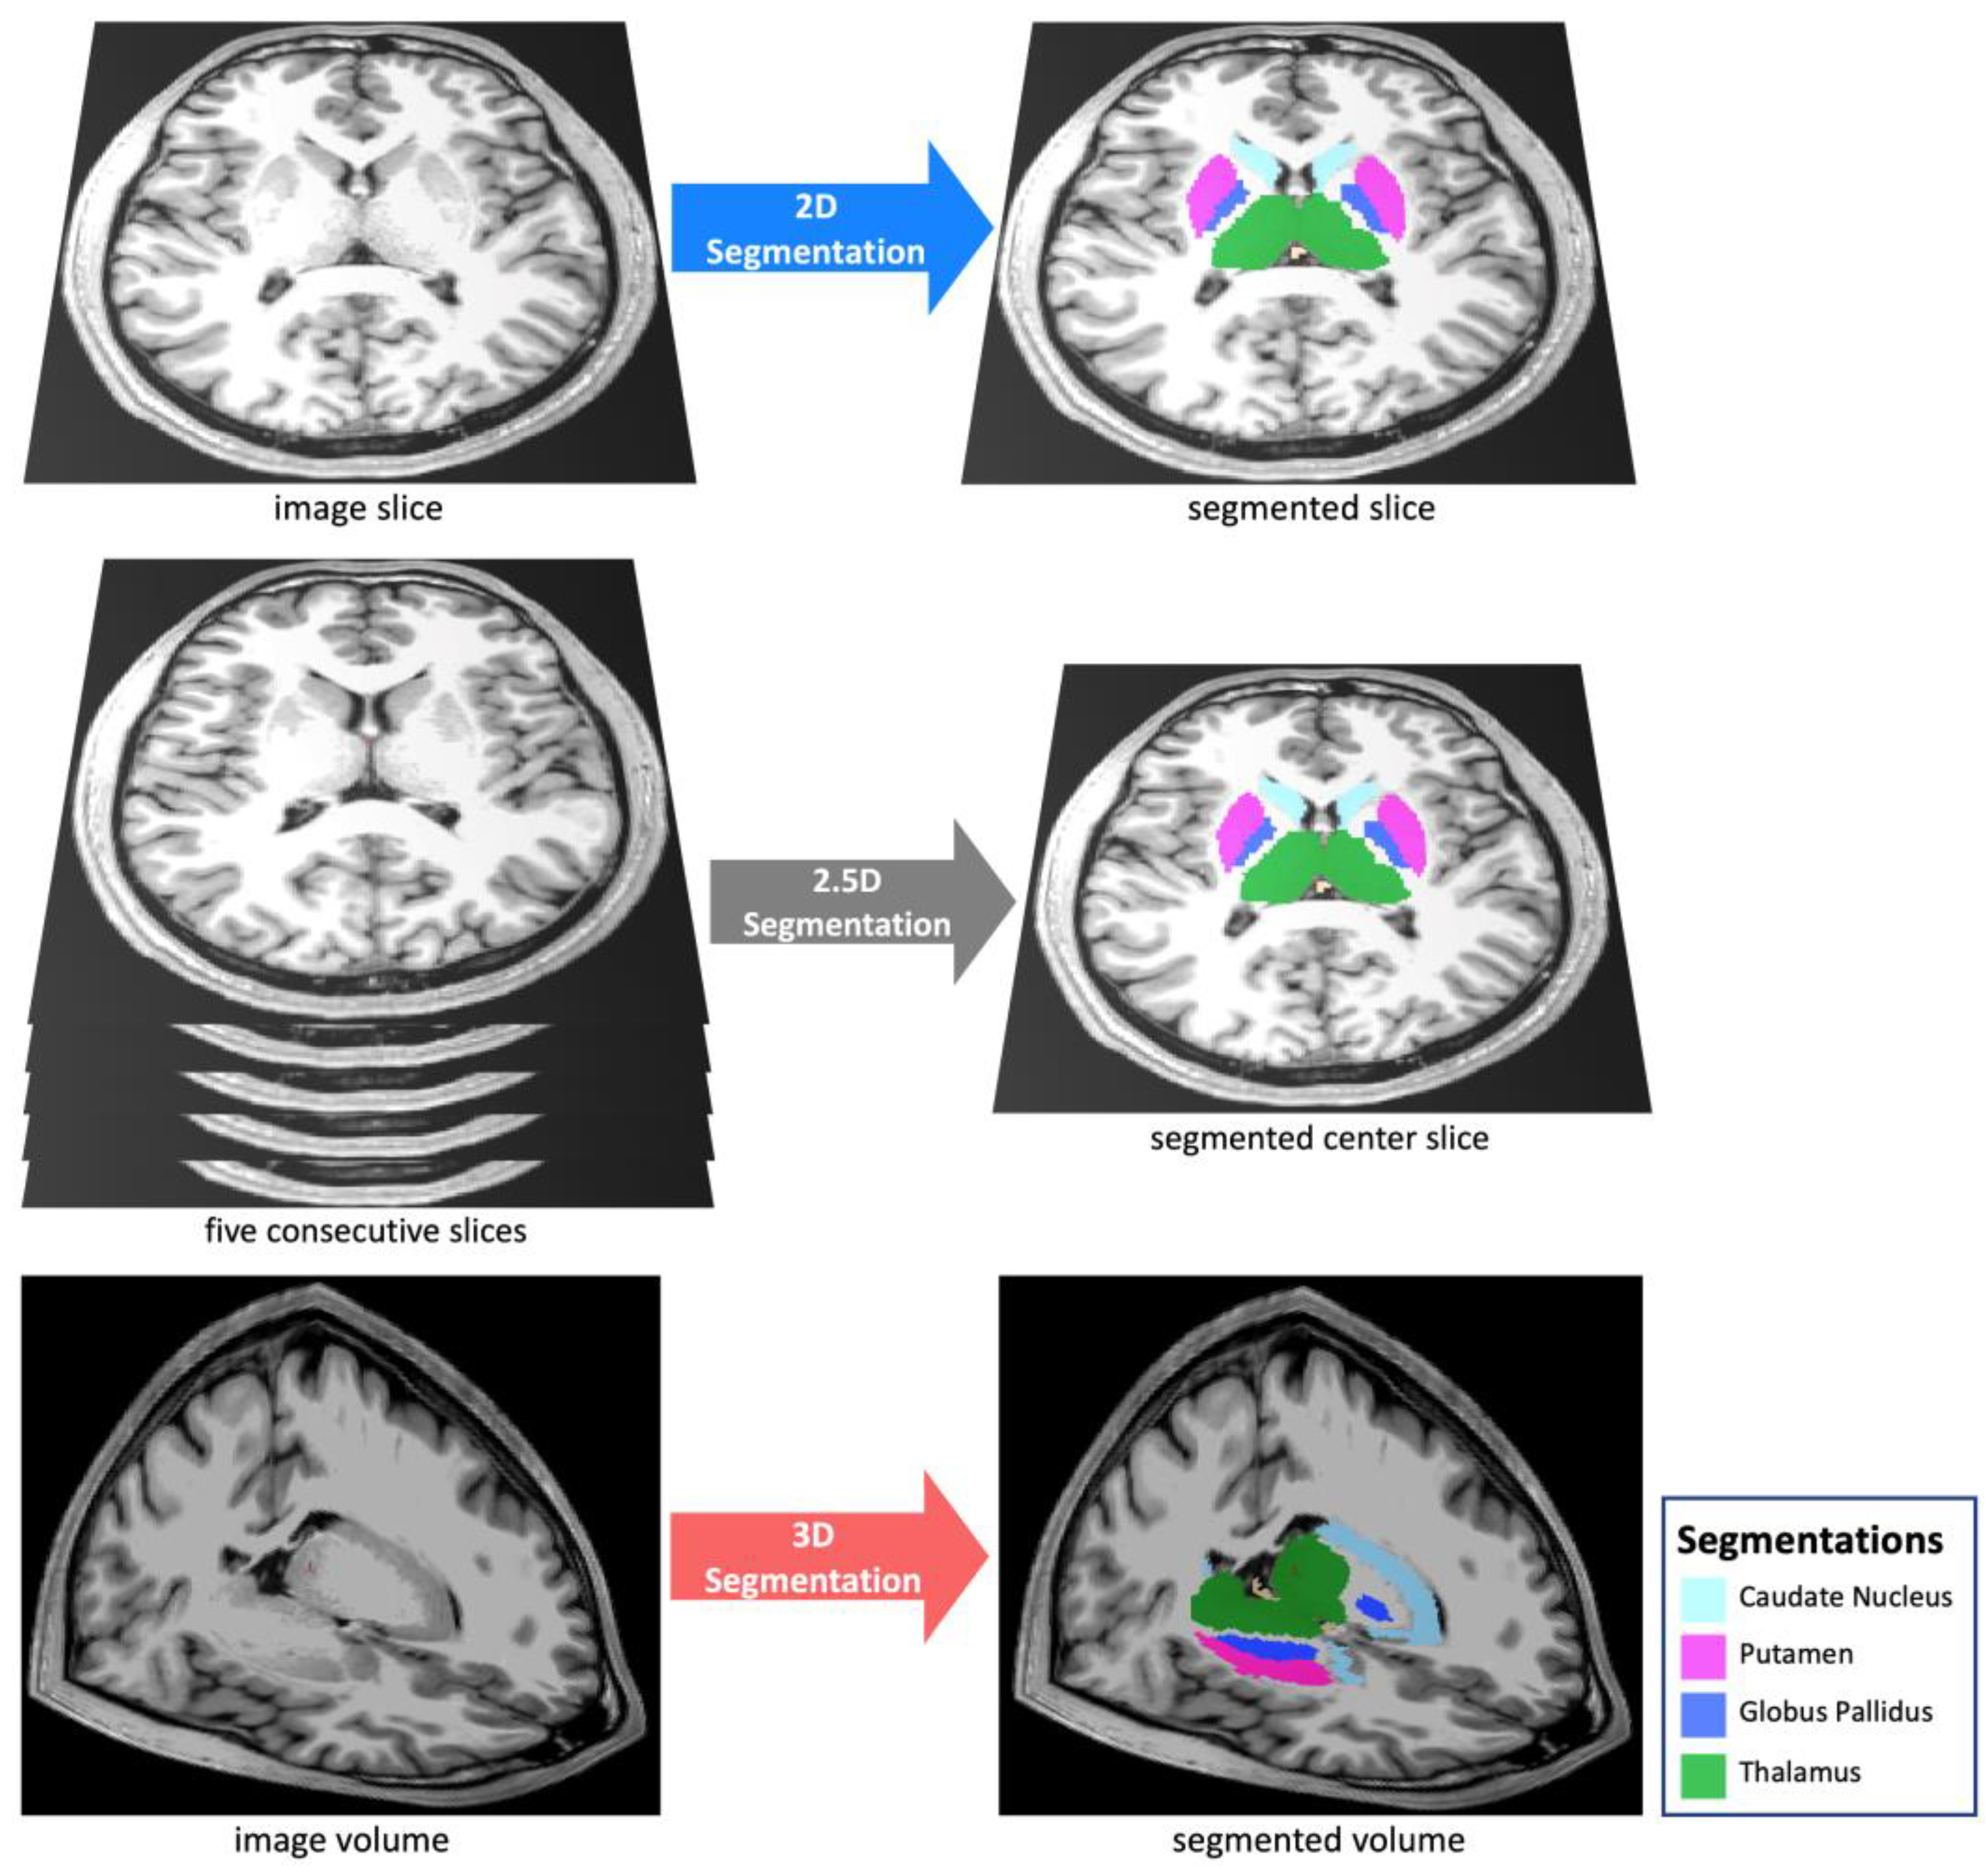

2.4. Auto-Segmentation Models